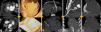

MethodsAll procedures were performed by experienced cardiologists or cardiac surgeons, using a Seldinger technique according to previously described protocols.17 CT guidance was obtained using a 64-slice scanner (Siemens SOMATOM Sensation, Erlangen, Germany) (Figure 1). Patients provided informed consent. During the procedure they were asked to breathe steadily and abstain from moving or breathing deeply. Local anesthesia with subcutaneous lidocaine was performed in every patient and light sedation (diazepam 5 mg orally) was administered when needed.

Use of computed tomography in pericardiocentesis. (a) Characterization and assessment of effusion; (b) determination of best entry point and needle orientation; (c) control of needle progression and relation with surrounding structures; (d) pigtail positioning; (e) final result and control of evolution.

Images of the whole thorax were acquired before the procedure and were analyzed with dedicated software (Siemens Syngo Viewer®). Parameters used by protocol were: tube voltage 100 kV, tube current 110 mAs, reconstruction with 0.75 mm sections, overlap 0.5 mm. Typical window width/level used during the procedure was 700/80. The best entry point and needle orientation were determined (Figure 1). We used an 18 gauge needle from the PeriVac™ kit (Boston Scientific®). After superficial needle insertion, new images of the area of interest were acquired. Needle orientation was corrected as needed and the needle was advanced under aspiration. New images were acquired as needed. When the pericardial space was reached, a drain (8.3F pigtail catheter from the kit) was inserted through a guidewire (J-tipped 0.035″×80 cm) and final images were acquired. When in doubt (due to limited pericardial width at the puncture site) a small amount of contrast (by protocol 5 ml diluted in 10 ml of saline) was injected to confirm an intra-pericardial needle position before dilation and drain insertion (Figure 2).